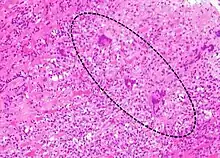

Most forms of myocarditis involve the infiltration of heart tissues by one or two types of pro-inflammatory blood cells, lymphocytes and macrophages plus two respective descendants of these cells, NK cells and macrophages. Eosinophilic myocarditis is a subtype of myocarditis in which cardiac tissue is infiltrated by another type of pro-inflammatory blood cell, the eosinophil. Eosinophilic myocarditis is further distinguished from non-eosinophilic myocarditis by having a different set of causes and recommended treatments.[34][18]

The gold standard is the biopsy of the myocardium, in general done in the setting of angiography. A small tissue sample of the endocardium and myocardium is taken and investigated. The cause of the myocarditis can be only identified by a biopsy. Endomyocardial biopsy samples are assessed for histopathology (how the tissue looks like under the microscope): myocardial interstitium may show abundant edema and inflammatory infiltrate, rich in lymphocytes and macrophages. Focal destruction of myocytes explains the myocardial pump failure.[10] In addition samples may be assessed with immunohistochemistry to determine which types of immune cells are involved in the reaction and how they are distributed. Furthermore, PCR and/or RT-PCR may be performed to identify particular viruses. Finally, further diagnostic methods like microRNA assays and gene-expression profile may be performed.